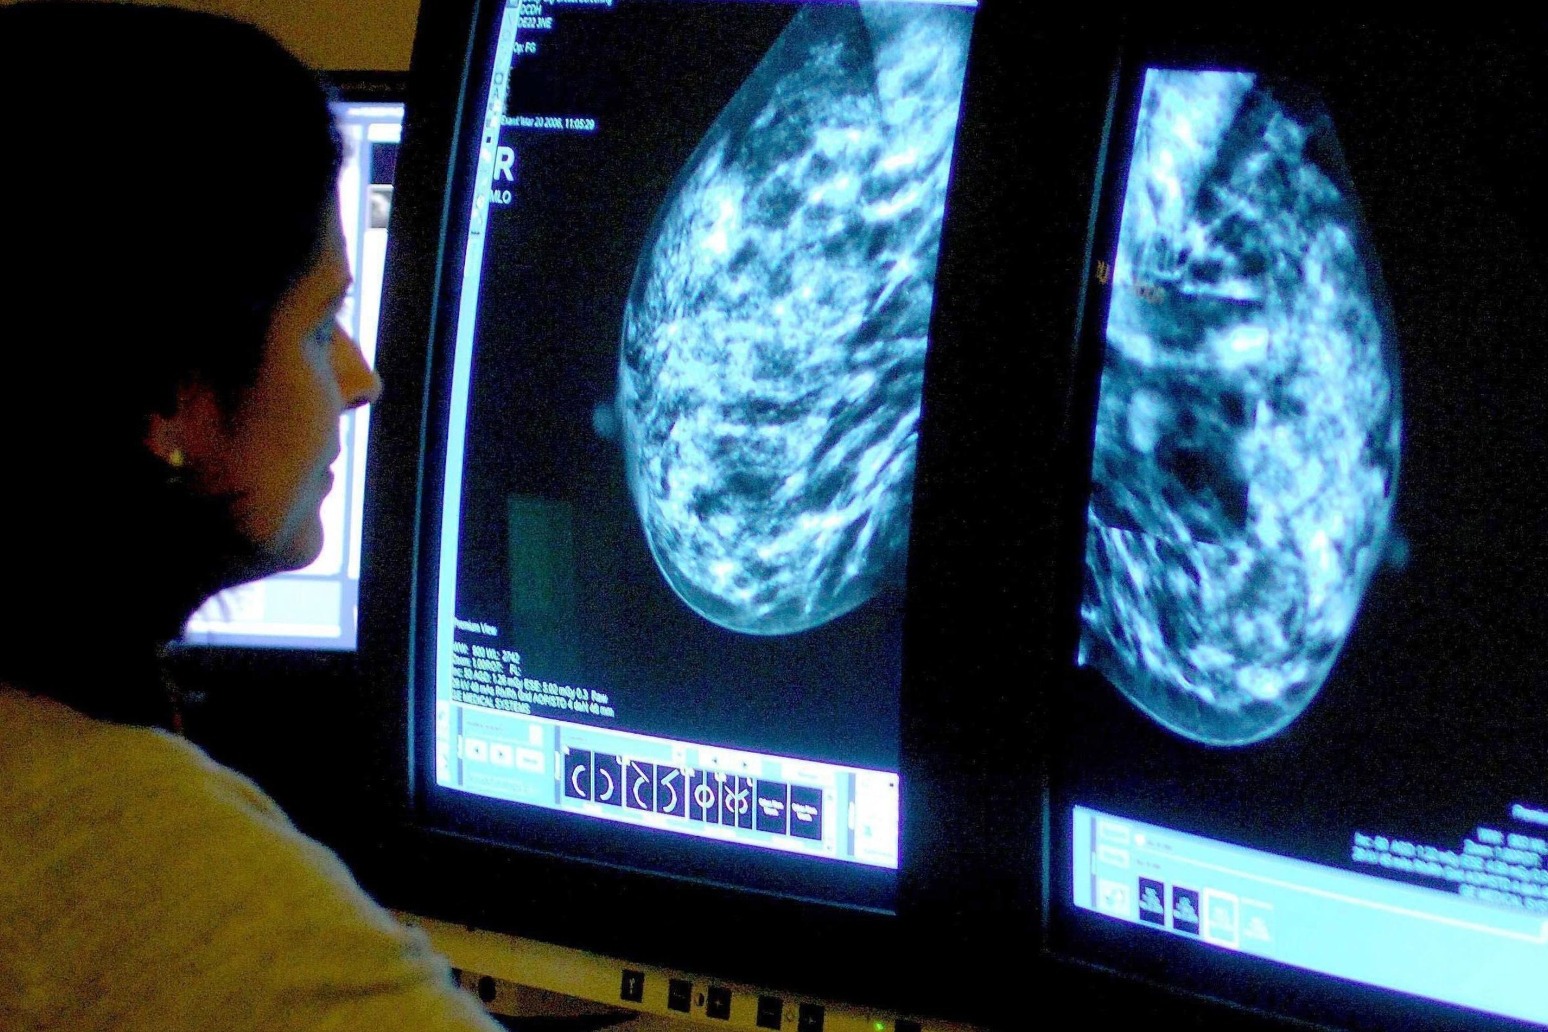

One in five women ‘have not checked for breast cancer signs in the last year’

That's according to a new survey conducted by YouGov

At least one in five women have not checked for signs of breast cancer in the last year, a YouGov poll suggests.